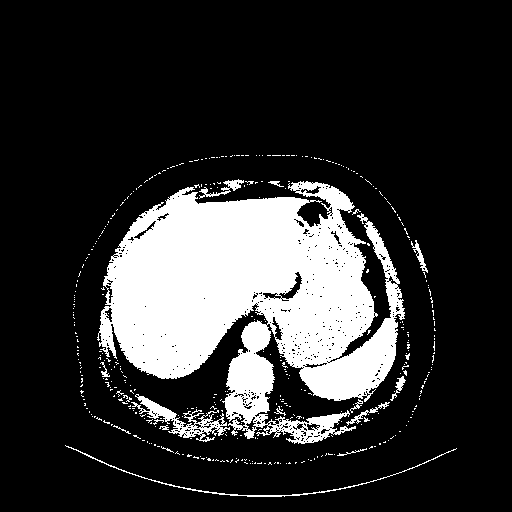

Original NATIVE CT scan (input)

Full window (WL 1023.5, WW 4095 β†’ Low βˆ’1024, High +3071)

Actual HU range: [-1024.0, 3071.0]